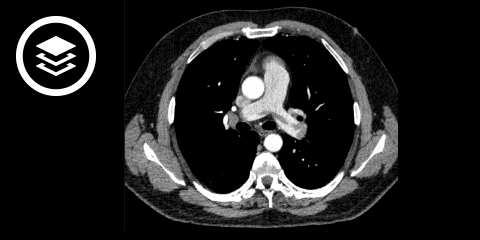

Ist nach den Voruntersuchungen eine Lungenembolie wahrscheinlich, sollte ein Embolusnachweis angestrebt werden. Die CT-Angiographie ist hierbei das Verfahren der 1. Wahl. Alternativ können eine MR-Angiographie, Lungenperfusionsszintigraphie oder eine Pulmonalisangiographie erfolgen.

CT-Fallbeispiel

- Bildquelle DICOM-Viewer: Datensatz freundlicherweise zur Verfügung gestellt durch die Klinik für diagnostische und interventionelle Radiologie, St. Vinzenz Hospital Köln